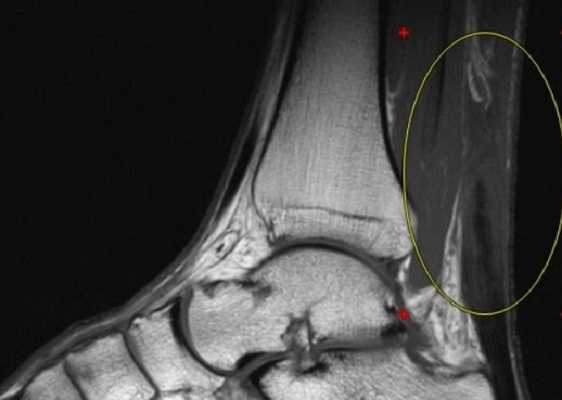

МРТ голеностопного сустава в сагиттальной плоскости. Отмечается полный разрыв пяточного сухожилия с признаками повреждения паратенона, реактивного паратендинита.